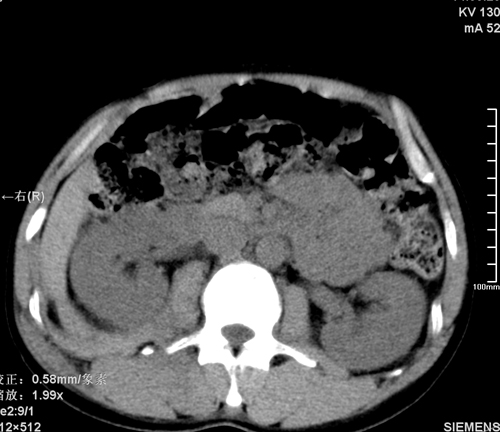

以下是引用tao772在2008-3-28 12:29:00的发言:[br]右侧腹膜后积血,右侧腰大肌挫伤,右侧部分横突骨折. 肾脏最好报一下挫伤,必要时增强。